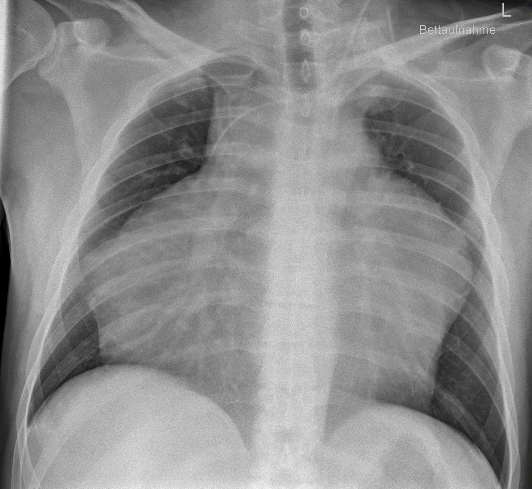

After sixth months, the patient presented with complaints of left sided chest pain and exertional dyspnoea, additionally to our clinic. He also reported position-dependent resting dyspnoea. On echocardiography he showed an unclear extracardiac mass with right-ventricular compression and functional right-ventricular outflow tract obstruction, but without features of restrictive physiology. Chest X-ray, computer tomography (CT) and CMR revealed a massive mediastinal bulk tumor causing complete encasement of the aorta and pulmonary artery, with no evident invasion of the peri- or myocardium (Figure). A CT-guided puncture within 24 hours resulted in the diagnosis of synovial sarcoma. Staging investigation revealed no further metastatic disease and emergency radiochemotherapy was initiated, achieving partial remission and resolution of symptoms after one cycle.

Figure: pa chest X-ray with central venous catheter and mediastinal bulk tumor.